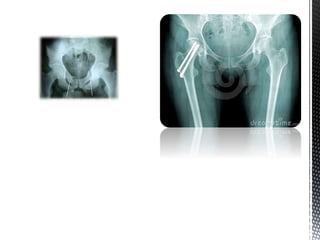

Quadril

As fraturas do quadril, em especial as que ocorrem na parte proximal do

fêmur, representam um sério problema de saúde publica, pela grande

frequência com que ocorrem e pela particularidade de maior incidência

Quadril As fraturas doquadril, em especial as que ocorrem na parte proximal do fêmur, representam um sério problema de saúde publica, pela grande frequência com que ocorrem e pela particularidade de maior incidência entre os idosos. Aproximadamente 90% delas comprometem pessoas acima de 65 anos. A incidência estimada dessas fraturas em mulheres que chegam aos 90 anos é de 33%, enquanto nos homens é de 16%.

“A maior incidênciade fraturas na velhice é explicada pela osteoporose, que contribui para a diminuição da resistência óssea, pelo déficit visual e pelo maior número de quedas. Além dessas causas, outras situações, como alterações da marcha e uso de tranquilizantes podem induzir também ao aumento do número de quedas e consequentemente de fraturas” quase sempre, em pacientes idosos, as fraturas que acometem a região do quadril são causadas por quedas da própria altura ou decorrente de mínima força rotacional lateral, como, por exemplo, tropeçar no chinelo ou no tapete.